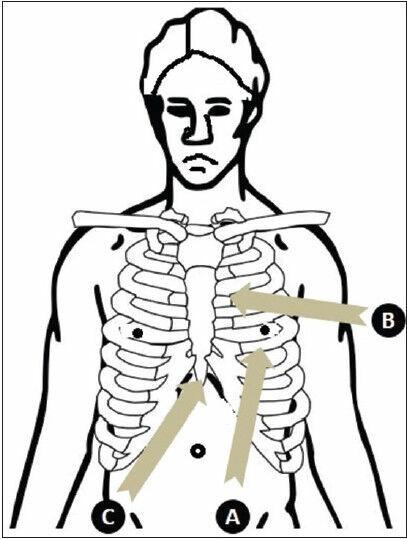

There is increasing interest in the use of ultrasound to assess and guide the management of critically ill patients. The ability to carry out quick examinations by the bedside to answer specific clinical queries as well as repeatability are clear advantages in an acute care setting. In addition, delays associated with transfer of patients out of the Intensive Care Unit (ICU) and exposure to ionizing radiation may also be avoided. Ultrasonographic imaging looks set to evolve and complement clinical examination of acutely ill patients, offering quick answers by the bedside. In this two-part narrative review, we describe the applications of ultrasonography with a special focus on the management of the critically ill. Part I explores the utility of echocardiography in the ICU, with emphasis on its usefulness in the management of hemodynamically unstable patients. We also discuss lung ultrasonography - a vastly underutilized technology for several years, until intensivists began to realize its usefulness, and obvious advantages over chest radiography. Ultrasonography is rapidly emerging as an important tool in the hands of intensive care physicians.

超声在评估和指导危重症患者管理方面的应用正受到越来越多的关注。在床边进行快速检查以回答特定临床问题的能力以及可重复性,在急性护理环境中具有明显优势。此外,还可避免与将患者转出重症监护病房(ICU)相关的延误以及暴露于电离辐射。超声成像似乎将不断发展并补充对急重症患者的临床检查,在床边提供快速答案。在这篇分两部分的叙述性综述中,我们描述超声检查的应用,特别关注危重症的管理。第一部分探讨超声心动图在ICU中的效用,重点是其在血流动力学不稳定患者管理中的作用。我们还讨论肺部超声检查——这项技术多年来未得到充分利用,直到重症医学专家开始认识到其效用以及相对于胸部X线摄影的明显优势。超声检查正迅速成为重症监护医师手中的一项重要工具。